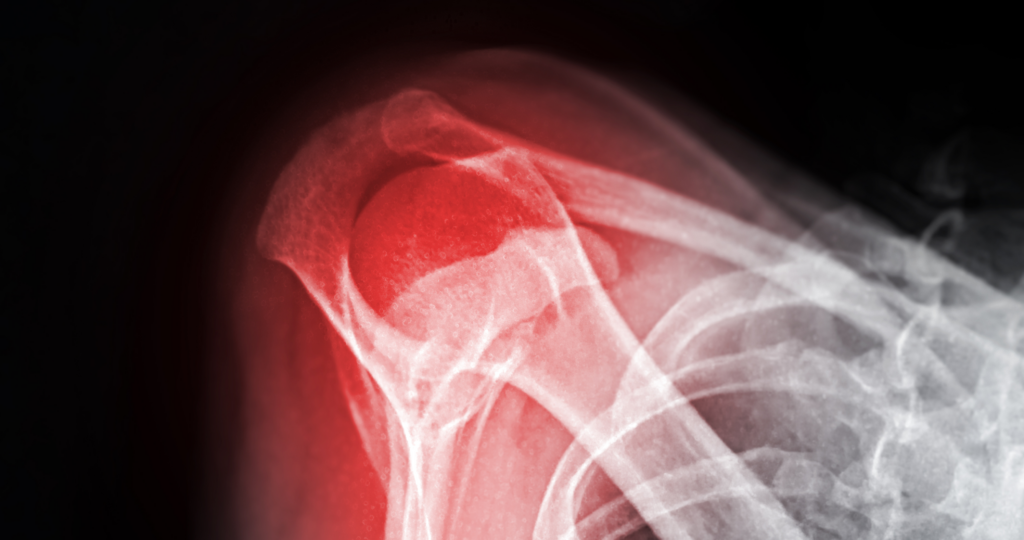

The shoulder joint represents one of the most mobile joints in the human body, allowing us to reach in virtually any direction. However, this mobility comes with less inherent bony stability compared to other joints, making the shoulder vulnerable to various injuries, including fractures. A shoulder fracture refers to a break in any of the three bones that form the shoulder complex. The proximal humerus is one of the most commonly fractured bones in the shoulder region, particularly in older adults. The clavicle is also frequently fractured, particularly in children, adolescents, and younger adults. Scapular fractures, while less common, typically result from high-energy trauma.

Shoulder fractured

Fractures can be classified in several ways. A closed fracture means the bone is broken but the skin remains intact, while an open fracture involves the broken bone piercing through the skin. Fractures can also be displaced, where fragments have moved out of alignment, or non-displaced, where pieces remain relatively close to their original position.